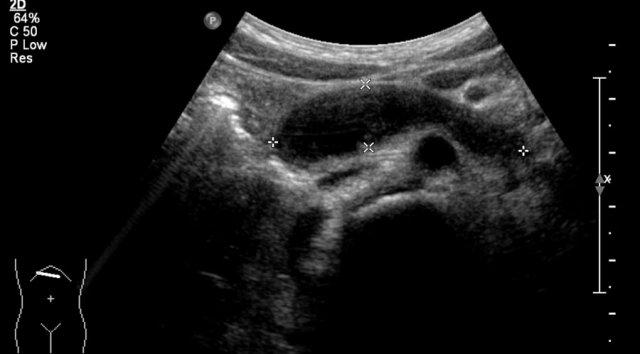

Trước sinh, thận trái được chẩn đoán có hệ thống đôi kèm ứ nước thận. Siêu âm sau sinh cho thấy một nang lớn ở cực trên thận trái và một số nang nhỏ hơn (không hiển thị trong hình).

Không thấy nhu mô thận bình thường.

Trên chụp bàng quang – niệu đạo khi tiểu (MCUG), thấy hình ảnh trào ngược vào hệ thống cực dưới, bị đẩy xuống dưới và xoay do khối ở cực trên.

Đây nhiều khả năng là MCKD khu trú ở cực trên.

MCKD có thể ảnh hưởng đến một cực của hệ thống đài bể thận đôi.